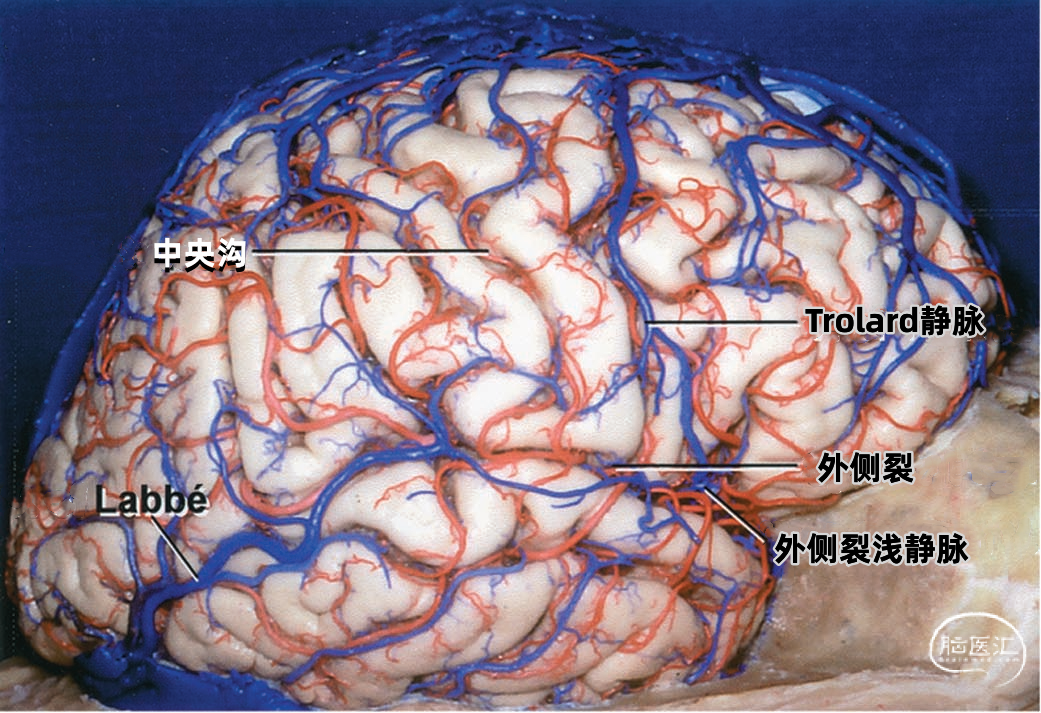

大脑外侧面最大的静脉是Trolard、Labbé、外侧裂浅静脉。 Trolard静脉是最粗大的吻合静脉,连接外侧裂静脉和上矢状窦。Labbé静脉则是连接外侧裂浅静脉和横窦的最粗大吻合静脉。外侧裂浅静脉沿外侧裂表面走行,而且主要沿蝶骨嵴汇入硬膜窦(蝶顶窦或海绵窦)。 虽然Trolard、Labbé静脉和外侧裂浅静脉大小可能相同,但更常见的是其中一支或两支血管比较粗大,而剩下的则细小甚至缺如。通常左右两侧血管的大小并不对称。

下图示三组吻合静脉,Trolard静脉和Labbé静脉为主要引流静脉。

▼1.Trolard静脉

Trolard静脉又称上吻合静脉,是跨越额叶和顶叶,连接外侧裂与上矢状窦的最大吻合静脉。 在我们研究的20例半球标本中,发现15例Trolard静脉的位置相当于中央前静脉、中央沟静脉和中央后静脉,最常见的位置是中央后静脉水平。最靠前的Trolard静脉位于额前静脉水平,连接上矢状窦的前部和外侧裂浅静脉的前部。最靠后的Trolard静脉位于顶前静脉水平。 Trolard静脉通常以单干向前走行,汇入上矢状窦,与血流相反方向。通常Troland静脉在将要汇入上矢状窦前接受其他一些静脉的回流,它的下端通常以单一通道与外侧裂静脉相沟通,但也可在额叶和顶叶凸面的下部分成许多分支加入外侧裂浅静脉。有时会有两条同样大小的Trolard静脉连接外侧裂血管和上矢状窦之间。

下图示(左侧半球)外侧裂浅静脉与Labbé静脉之间有较大的吻合支。另外,有两支或双干型的Trolard静脉属支连接上矢状窦和外侧裂静脉,后方一支Trolard静脉在外侧裂浅静脉与Labbé静脉的结合处附近加入外侧裂浅静脉。

下图示(右侧半球)双干型的Trolard静脉连接于上矢状窦和外侧裂之间,一支越过额叶,另一支越过顶叶。外侧裂浅静脉与Labbé静脉之间也有一个粗大的吻合支。